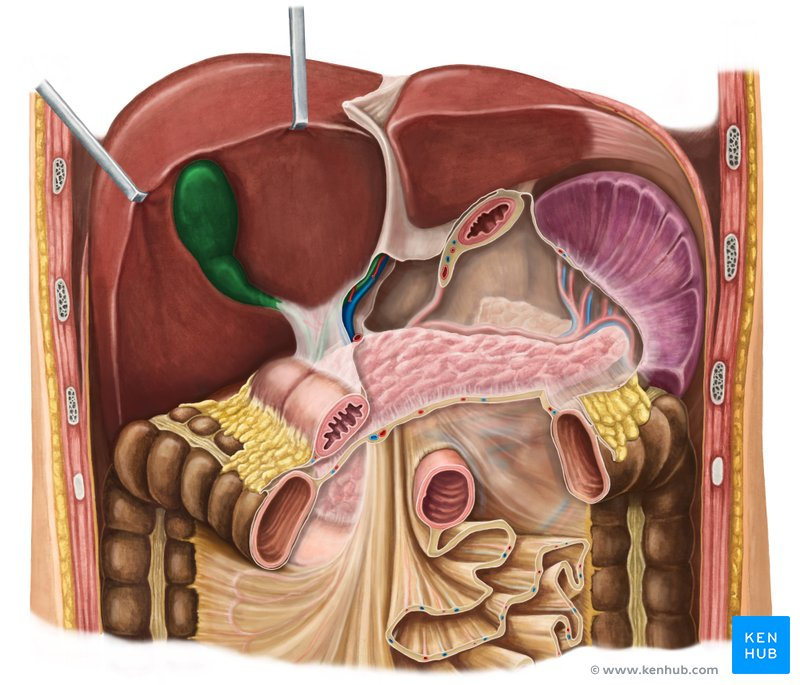

Liver

a large organ located in the upper right abdomen that produces bile, detoxifies blood, and performs many other metabolic functions.

Pancreas

a gland located behind the stomach that produces digestive enzymes and hormones like insulin and glucagon.

Small intestine / colon

the part of the digestive tract located between the stomach and the large intestine, where most of the digestion and absorption of nutrients occurs.

a J-shaped organ located in the upper abdomen that stores, mixes, and digests food.

Spleen

An organ located in the upper left abdomen that is part of the lymphatic system, filtering blood and storing white blood cells

Large intestine / colon

the final section of the digestive tract, responsible for absorbing water and electrolytes and forming feces.

Pancreas

A gland located behind the stomach that produces digestive enzymes and hormones like insulin and glucagon.

Mesocolon

A fold of peritoneum that attaches the colon to the posterior abdominal wall.

Gallbladder

A small, pear-shaped organ located beneath the liver that stores and concentrates bile produced by the liver.